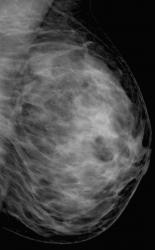

привожу случай снова.В верхне-наружном квадранте левой молочной железы отмечаются сгруппированные микарокальцианты без явной принадлежнсти к узловому образованию

Пациентка прооперирована. Гистология по cito: инфильтрирующий рак с участками слизистого рака.

Спасибо за случай. По большому счету, конечно, кое, что исчезло. Но большинство иллюстрации наших пользователей продублировано и никуда не делось. Имею вопрос. Рак ьыл обнаружженов зоне микрокальцинатов или нет?